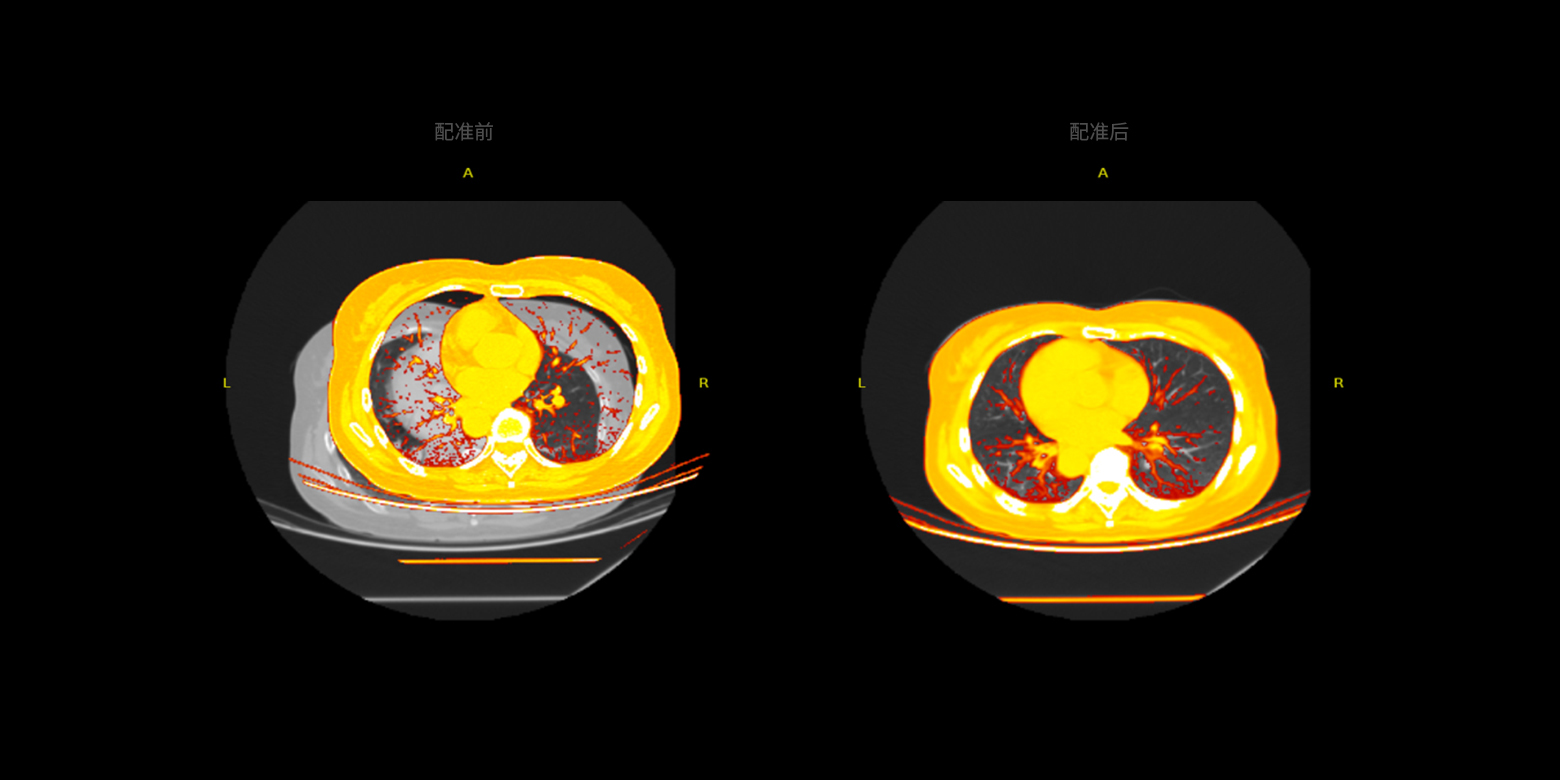

多模态数据的配准

支持同一部位或器官的 CT、MRI、PET 等多模态数据的配准,实现不同模态或不同序列数据之间精确的图像融合,从而能够更精准地对病灶进行定性分级或定量分析。